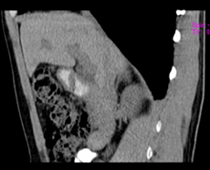

患者,男,57,常年不吃午饭,近一个月来腹部隐痛,无明显黄疸,明天进行增强扫描,图象另上传,麻烦各位帮忙一起看看讨论讨论

肝外胆管扩张,胰头增大,肠系膜上静脉似有包埋征象。

考虑:胰头占位性病变,建议增强进一步检查。

肝外胆管稍扩张,胰腺钩突略增大,但外形尚可,境界清楚。(常年不吃午饭)提示胰腺炎可能大,肿瘤第二步考虑。

支持考胰头占位性病变,感觉十二指肠壁不规则增厚,不排除十二指肠降部占位可炎症

胰头增大,胆总管增宽,考虑胰头癌可能性大,明天看增强片有助诊断.